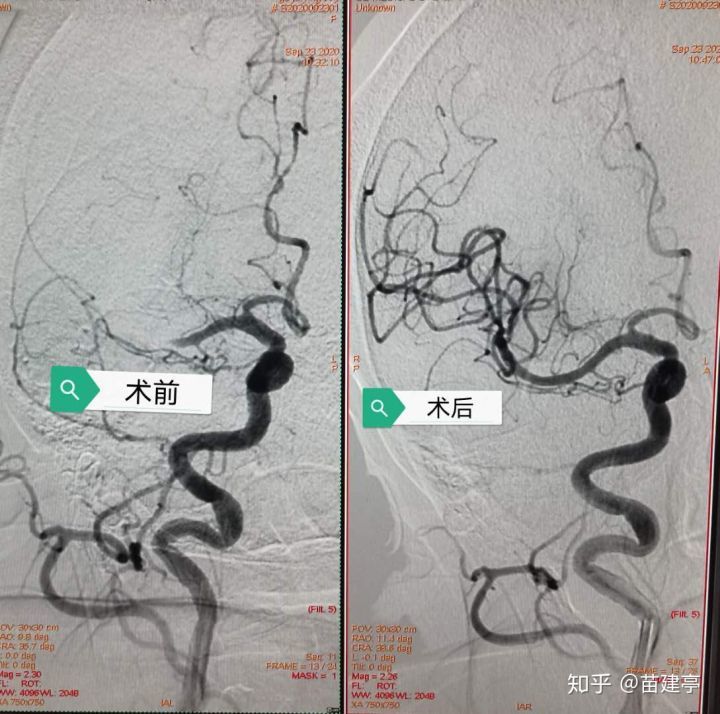

接到急诊通知后 , 作为卒中中心医护人员 , 深知时间就是大脑 , 立即启动脑卒中绿色通道 , 卒中医护携带卒中箱 , 快速前往核磁共振室 , 有序完成影像学检查 , 核磁共振血管成像示:右侧大脑中动脉闭塞 。 经过精准的评估 , 张冬子执行院长耐心地与患者家属沟通手术的利与弊 , 在家属充分理解与信任下 , 急诊在局麻下行股动脉造影桥接右侧大脑中动脉机械取栓术 。

核磁共振血管成像示:右侧大脑中动脉闭塞

取栓后血管成像示:右侧大脑中动脉完全再通